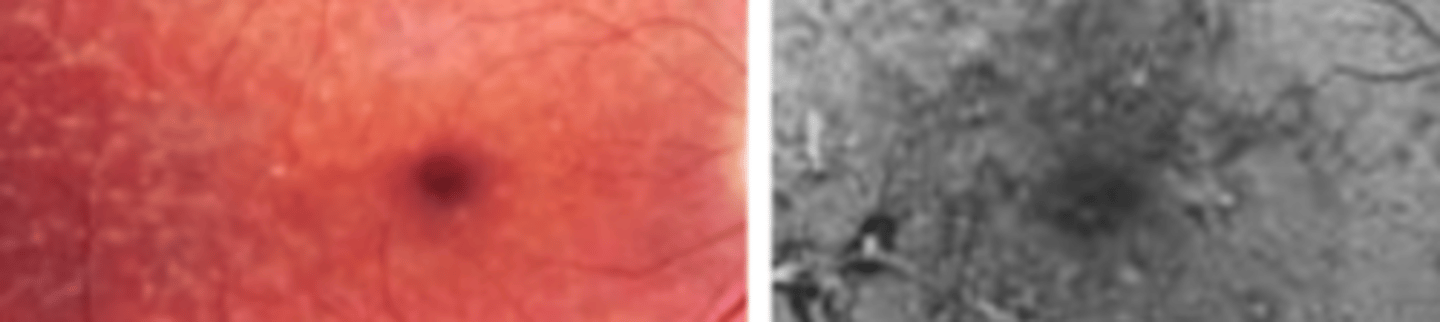

Stargardt Disease (juvenile macular dystrophy)

CONE rod dystrophy which is an autosomal recessive disease causing a mutation of the ABCA4 gene. Presents as bilateral gradual impairment of central vision in the 1st to 2nd decade which may be out of proportion to macular changes which may be appointed to malingering since patients are young. Poor prognosis with no treatment. Genetic counseling and low vision devices are available.

Photopic ERG, pattern ERG

two electrodiagnostic tests that are useful in the early diagnosis of Stargardt disease

Kollner's rule

Upon color vision testing Stargardt disease is an exception to...

Thickened ELM, EZ line absent at the fovea

two findings of Stargardt disease seen on OCT

Fundus Flavimaculatus

an autosomal recessive disease that is considered Stargardt disease presenting in adulthood in the absence of macular involvement. Presents as pisciform yellow white flecks scattered throughout the posterior pole. Good prognosis due to later onset and minimal maculopathy. Geographic atrophy rarely occurs.